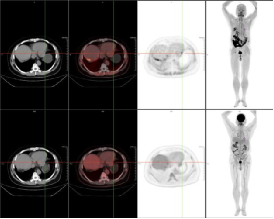

例二:79岁老年女性,胆囊结石7年,现反复腹痛待查,临床高度怀疑胰腺癌。传统影像学检查未能明确病灶边界与转移范围,通过18F-FAPI PET/CT显像,确诊为肝左外叶肝内胆管细胞癌(ICC),左侧锁骨旁、纵隔内(4R、4L、5、6、7)及双侧肺门、腹腔内、肝胃间隙、腹膜后、腹主动脉左旁、盆腔内多发淋巴结转移灶,胰腺及腹主动脉受侵。

新型分子探针18F-FAPI清晰呈现了原发灶及转移灶的精准位置、大小及周围组织侵犯情况,同时发现了隐匿的转移灶,为临床制定个体化治疗方案提供了关键依据。为肿瘤患者病灶的精准识别带来福音,为临床及时调整治疗策略、改善预后创造了条件。